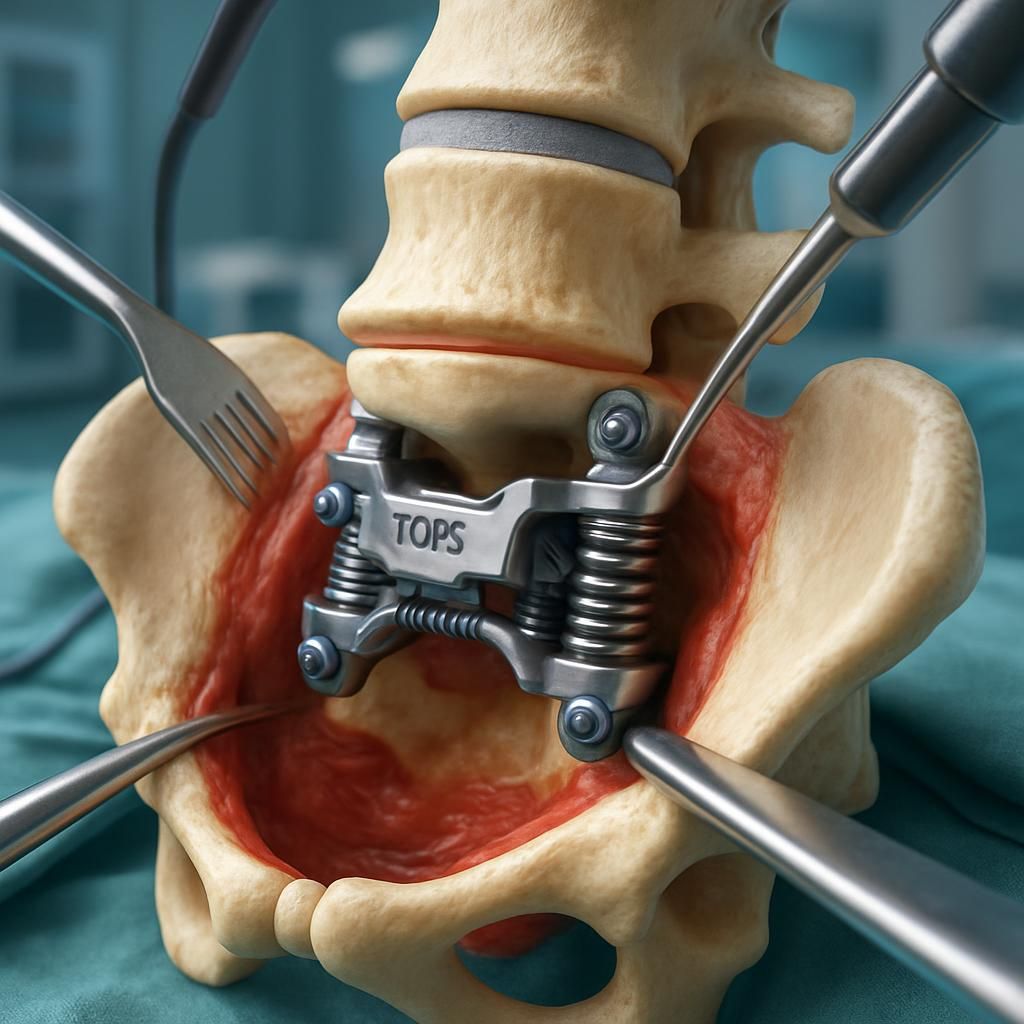

Parmi ces innovations, le système TOPS (Total Posterior Spine System) et l’implant IntraSPINE se distinguent par leur capacité à préserver le mouvement naturel tout en stabilisant la colonne vertébrale. Le système TOPS agit comme un stabilisateur postérieur intelligent qui contrôle les mouvements excessifs au niveau d’une vertèbre tout en permettant une certaine flexion, extension et rotation. L’implant IntraSPINE, quant à lui, est positionné dans l’espace interépineux pour soutenir la colonne et réduire la charge sur les disques vertébraux, favorisant ainsi une protection durable du rachis.

Ces implants dynamiques sont synonymes d’une réduction des douleurs post-opératoires, d’une récupération fonctionnelle plus rapide et d’une meilleure qualité de vie à long terme. Ils illustrent un progrès important en matière de biomécanique rachidienne, combinant sécurité et innovation technique, deux priorités systématiquement mises en avant par les experts lyonnais et par les réseaux cliniques associés. Pour mieux comprendre ces solutions, il est recommandé de consulter des explications détaillées sur la fusion vertébrale et les alternatives modernes dans le domaine de la chirurgie rachidienne, disponibles sur ce site dédié.